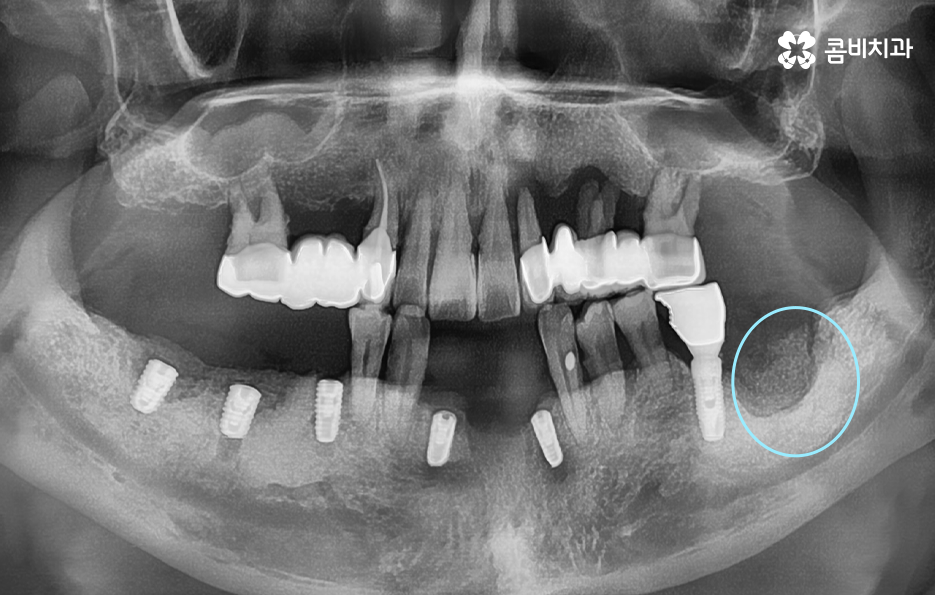

위 환자분의 케이스를 살펴보면 임플란트 시술 후 임플란트 주위염이 발생되어 이미 치조골이 상당히 녹았을 정도로 엑스레이 상에서도 관찰할 수 있어요

임플란트는 보편적으로 분리형이 주로 사용되고 있는데 임플란트의 인공치근은 잇몸 뼈와 골유착이 되어 단단하게 고정이 되어 있고 그 위에 지대주와 보철물이 연결되어 있는 형태이기 때문에 임플란투 수명에 있어서 임플란트의 인공치근 부분이 염증으로 인해 잇몸 뼈가 녹게 되면 임플란트 자체도 흔들리게 되고 결국 제거 후 재수술을 해야 될 수 있어요

흔히 임플란트 시술을 잘하면 약 10년이나 15년 이상도 사용할 수 있을거라 예상하는 분들이 많은데 실제로 15년 이상도 잘 사용하시는 분들도 많지만 사후관리가 잘 안되면 수년만에 임플란트 주위염과 같은 부작용이 발생될 수도 있다는 점에서 지속적인 사후관리가 중요한 시술이라고 생각하시면 좋을 거예요